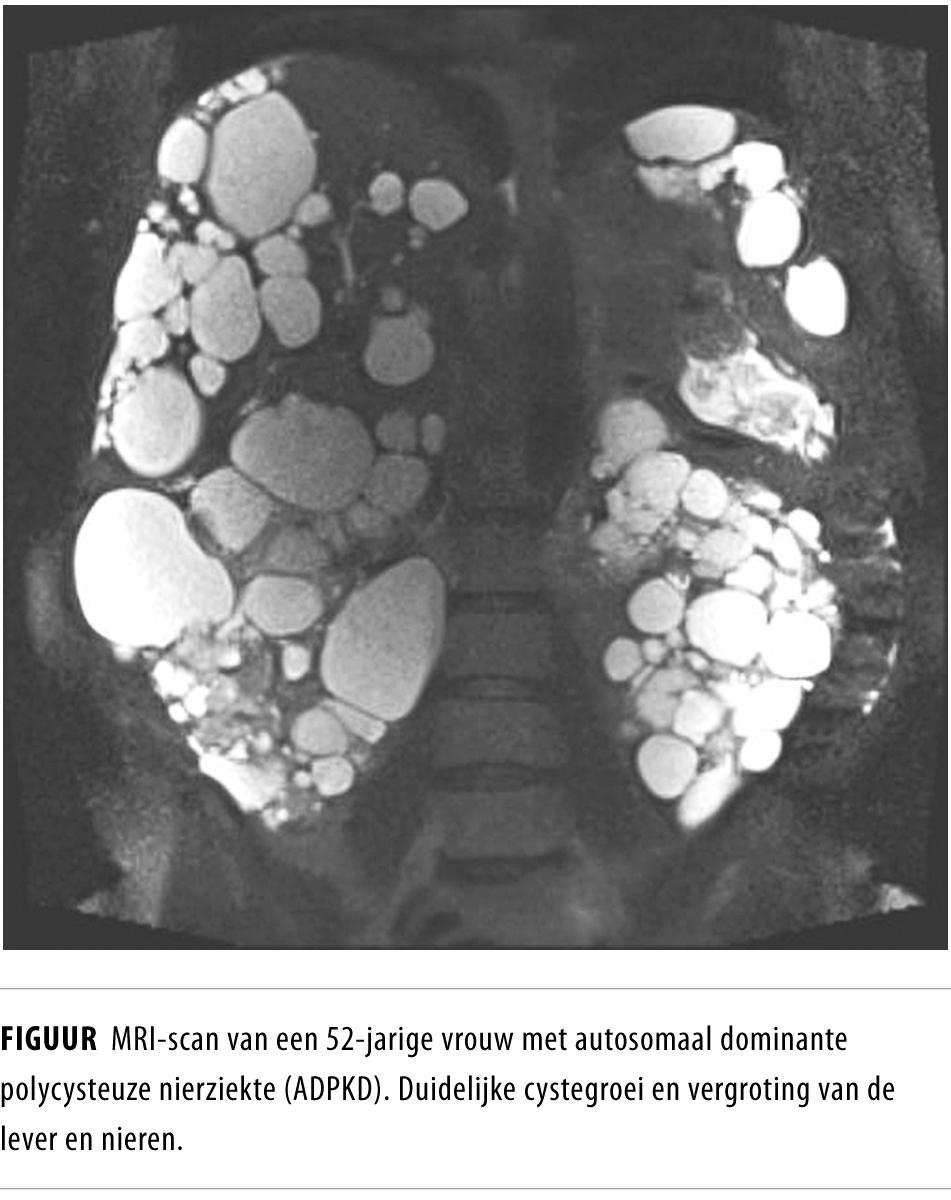

Autosomaal dominante polycysteuze nierziekte (ADPKD), of vaak kortweg cystenieren genoemd, is een erfelijke ziekte. Kenmerkend is de vorming van grote cysten in de nieren (obligaat) en in de lever (figuur 1). De belangrijkste complicatie is het optreden van progressief nierfalen. De meeste patiënten moeten tussen hun 40e en 70e levensjaar starten met nierfunctievervangende therapie.1 Door de groei van deze aangedane organen kunnen ook andere klachten ontstaan zoals buikpijn, anorexie en malaise. Ook kunnen de cysten leiden tot complicaties zoals rupturen, bloedingen en infecties. Ongeveer 10% van alle patiënten die nierfunctievervangende behandeling krijgen, heeft ADPKD. Tot voor kort waren er geen therapieën die de cystegroei konden afremmen.2 Recent is gebleken dat een vasopressine V2-receptorantagonist de cystegroei in de nieren remt bij patiënten met een goede nierfunctie.3 Dit medicament heeft echter aanzienlijke bijwerkingen, zoals polyurie en dorst. Ook is het mogelijk niet effectief in een later stadium van de ziekte en heeft het waarschijnlijk geen effect op levercysten.4 In kortdurende, kleinschalige studies is aangetoond dat somatostatine-analogen (lanreotide en octreotide) de groei van levercysten kunnen remmen.1,5-8 Er kon echter geen uitspraak gedaan worden over het effect op de achteruitgang van de nierfunctie.

De DIPAK1-studie is een gerandomiseerde klinische studie, die wordt uitgevoerd in meerdere centra en wordt gefinancierd door de Nierstichting. Wij randomiseren 300 patiënten met ADPKD (diagnose gebaseerd op de Ravine-criteria)9 van 18-60 jaar, met een afgenomen nierfunctie (geschatte glomerulaire filtratiesnelheid (eGFR): 30-60 ml/min/1,73 m2) voor behandeling met lanreotide (subcutane injectie van 120 mg of 90 mg als de eGFR < 30 ml/min) die elke 4 weken wordt toegediend) of standaardzorg (controlegroep). De studie duurt 3 jaar. Aan het begin en eind van de studie wordt er een MRI van de nieren en de lever verricht. Daarnaast wordt de patiënt in die periode van 3 jaar in totaal 14 keer ter controle gezien, waarbij bloed en urine wordt afgenomen. Jaarlijks moet een vragenlijst worden ingevuld. De studie is in juli 2012 gestart en wordt uitgevoerd in het Erasmus MC, het LUMC, het UMCG en het UMC St Radboud.